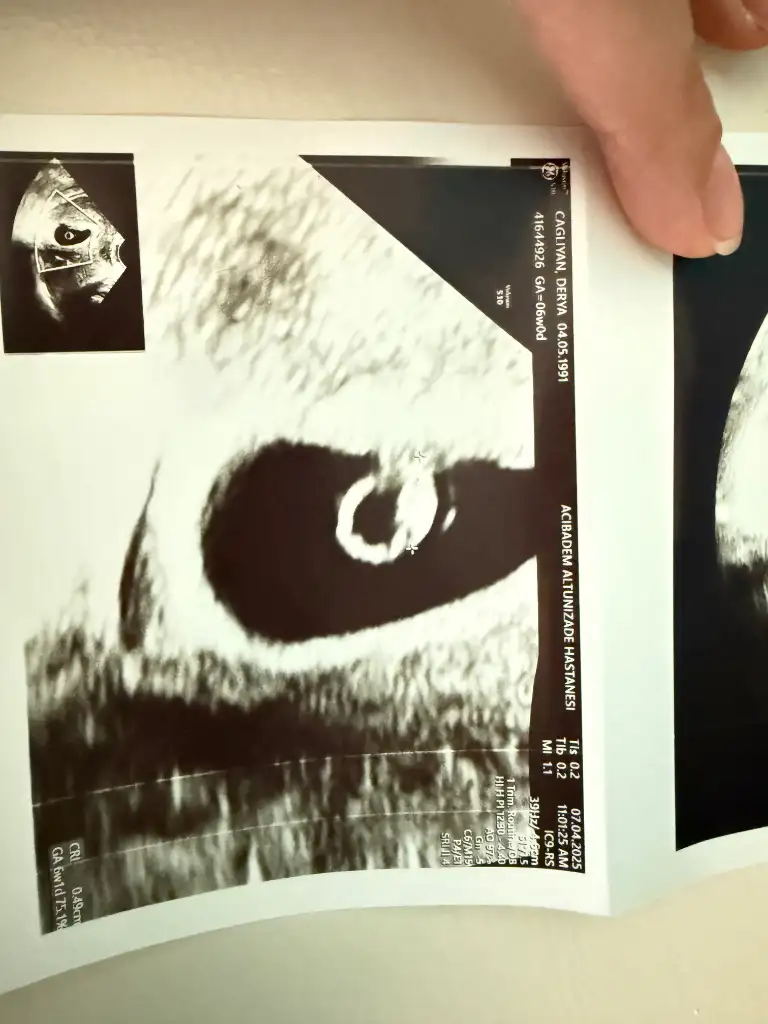

İlk defa böyle bişey yapıyorumKızlar 6-8 haftalık ultrason görüntülerinizi atın tahmin yapalım . Ya da cinsiyeti öğrenen annelerimiz 6-8 haftalık görüntülerini atsın bize de fikir olsun

Yazmayı unuttum vajinalKızlar 6-8 haftalık ultrason görüntülerinizi atın tahmin yapalım . Ya da cinsiyeti öğrenen annelerimiz 6-8 haftalık görüntülerini atsın bize de fikir olsun

Kız olabilir diye düşünüyorumİlk defa böyle bişey yapıyorumhenüz çok erken 6+1 burada, inşallah sağlıkla devam eder ama konuyu görünce de dayanamadım yorumunuzu beklerim

Abdominal görüntüyse eğer kız olabilirBenimkide 6 buçuk haftalık görüntü çok belli değil sanki ama yorumlayabilen varsa beklerim